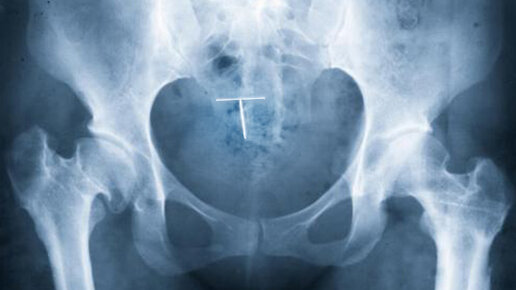

"Сбежавшая спираль"

Общеизвестно, что первым этапом обследования гинекологических пациенток служит УЗИ. Однако бывают случаи, когда по каким-то причинам врачу недостаточно данных УЗИ. Что поможет врачу сделать правильный выбор в пользу того или другого дополнительного обследования? Знания о возможностях и ограничениях других методов визуализации, например, МРТ и МСКТ. Многие гинекологи назначают МРТ малого таза для исключения/подтверждения патологии женских половых органов, например, при дифференциальной диагностике заболеваний, вызывающих боли внизу живота...